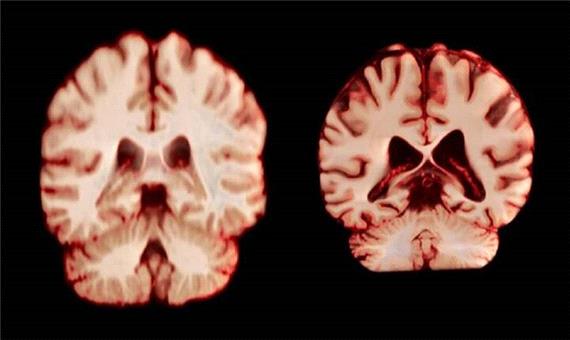

مغز مردان سریع‌تر از زنان کوچک می‌شود

سیاست و بازاریابی - ایسنا / مغز زنان کُندتر پیر می‌شود، اما به نظر نمی‌رسد که این موضوع آنها را از ابتلا به نوع شایع زوال عقل محافظت کند.

بر اساس یک مطالعه طولی که امروز در مجموعه مقالات آکادمی ملی علوم منتشر شد، در طول پیری، مردان در مقایسه با زنان، کاهش حجم بیشتری را در مناطق بیشتری از مغز تجربه می‌کنند. نویسندگان معتقدند این بدان معناست که تغییرات مغزی مرتبط با سن توضیح نمی‌دهد که چرا زنان بیشتر از مردان به بیماری آلزایمر مبتلا می‌شوند.

زنان تقریبا دو برابر مردان به بیماری آلزایمر مبتلا می‌شوند و پیری بزرگترین عامل خطر برای این بیماری است. این موضوع باعث شده است که تحقیقاتی در مورد تفاوت‌های جنسیتی مرتبط با سن در مغز انجام شود. آن راوندال، دانشجوی دکترا در دانشگاه اسلو و یکی از نویسندگان این مقاله، می‌گوید: اگر مغز زنان بیشتر تحلیل رفته باشد، این می‌تواند به توضیح شیوع بالاتر آلزایمر در آنها کمک کند.

راوندال اضافه می‌کند که تحقیقات قبلی که تفاوت‌های جنسیتی در پیری مغز را بررسی می‌کردند، نتایج متفاوتی را نشان داده‌اند. چندین مطالعه نشان داده‌اند که مردان در مقایسه با زنان، کاهش بیشتری در کل ماده خاکستری و اندازه هیپوکامپ را تجربه می‌کنند، در حالی که سایر تحقیقات، کاهش شدیدتر ماده خاکستری در زنان را گزارش کرده‌اند.

اسکن مغز

جدیدترین مطالعه شامل بیش از 12 هزار و 500 اسکن مغزی تصویربرداری تشدید مغناطیسی (MRI) از 4726 نفر بود که حداقل دو اسکن برای هر نفر، با فاصله متوسط ‌سه سال انجام شده بود که به بیماری آلزایمر یا هرگونه اختلال شناختی مبتلا نبودند و به عنوان شرکت‌کننده کنترل در 14 مجموعه داده بزرگتر قرار داشتند. محققان با بررسی عواملی از جمله ضخامت ماده خاکستری و اندازه نواحی مرتبط با بیماری آلزایمر، مانند هیپوکامپ که برای حافظه ضروری است، نحوه تغییر ساختار مغز افراد را در طول زمان مقایسه کردند.

به طور کلی، مردان در مقایسه با زنان، کاهش حجم بیشتری را در مناطق بیشتری از مغز تجربه کردند. به عنوان مثال، قشر پس مرکزی که مسئول پردازش احساسات لامسه، درد و دما و همچنین موقعیت و حرکات بدن است، در مردان سالانه 2.0 درصد و در زنان سالانه 1.2 درصد کاهش یافت.

کامفور می‌گوید نتایج نشان می‌دهد که مردان سریع‌تر از زنان پیر می‌شوند. همچنین امید به زندگی در مردان کمتر است.

ایمی برادتمن، محقق بالینی در حوزه سلامت شناختی در دانشگاه موناش در ملبورن استرالیا، می‌گوید اگر این تغییرات نقشی در ابتلا به بیماری آلزایمر داشتند، این مطالعه نشان می‌داد که زنان در نواحی مرتبط با این بیماری، مانند هیپوکامپ که در حافظه نقش دارند، کاهش بیشتری را تجربه می‌کنند.

راوندال می‌گوید نتایج به توضیحات احتمالی دیگری برای تفاوت‌های جنسیتی در شیوع بیماری آلزایمر، مانند تفاوت در بقا یا آسیب‌پذیری در برابر بیماری اشاره دارد.